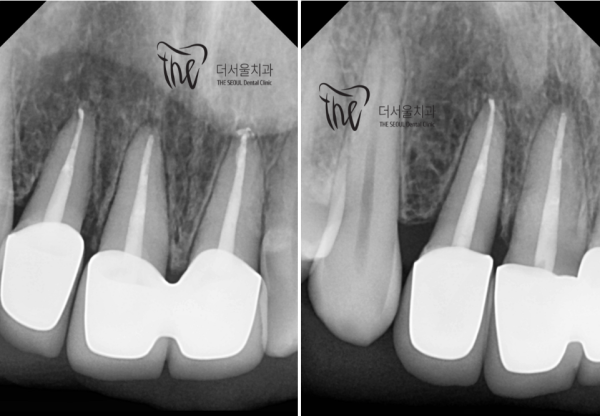

환자분의 문제가된 치아의 치수 속을 깨끗하게 청소한 후에 마스터콘이라는

충전재료를 꼼꼼히 넣은 모습입니다. 뿌리끝에서부터 빈틈없이 채워넣는 것이 아주 중요합니다.

이렇게 해야 문제가 재발하지 않게된답니다.

After cleaning the inside of the teeth in question, the master cone

It looks like you put in the filling ingredients carefully. It's very important to fill it in thoroughly from the root end.

This way, the problem will not recur.

그리고 치아의 모양대로 잘 만든 크라운을 셋팅하면 신경치료가 끝이 나게됩니다.

치료후에 다시 찍은 치근단 엑스레이를 보면 기존에 있던 뿌리쪽 염증이 모두 가라앉은 것을 확인할 수 있습니다.

그리고 바로 위의 사진과 비교해보면 크라운이 잘 올라가 있는것을 확인할 수 있습니다.

And if you set up a well-made crown in the shape of your teeth, nerve treatment will be over.

If you look at the root end X-ray taken again after treatment, you can see that all existing root inflammation has subsided.

And if you compare it to the picture right above, you can see that the crown is well raised.